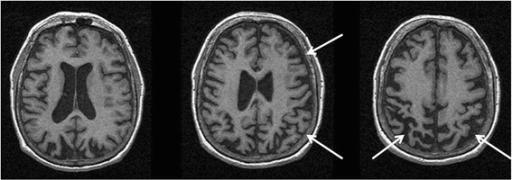

MRI showing right greater than left parietofrontal atrophy

MRI images are useful in displaying atrophied portions of neuroanatomical positions within the brain. As a result, it is especially effective in identifying regions within different areas of the brain that have been negatively affected due to the complications associated with CBD. To be specific, MRI of CBD typically shows posterior parietal and frontal cortical atrophy with unequal representation in corresponding sides. In addition, atrophy has been noted in the corpus callosum.[19]